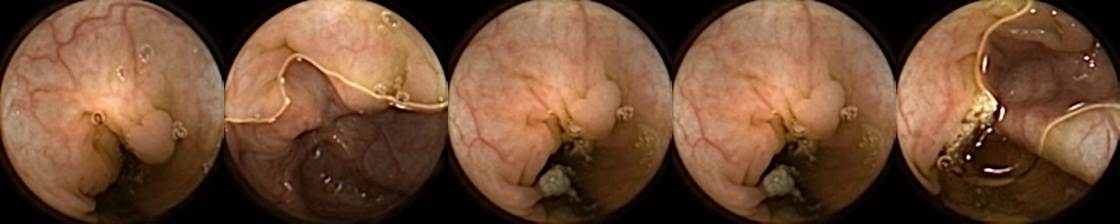

We can additionally consider the confusion matrices from the best MIV model associated with (a) the pretrained ConvNext and (b) SimCLR pretraining using the ConvNext backbone in Figure 5. We note that using SimCLR achieves a better ratio of False Negatives (70) to False Positives (38) as compared to pretrained ConvNext, which has 109 False Negatives and 23 False Positives.

Refer to caption

Figure 5: Confusion matrices from the best MIV model associated with (left) the pretrained ConvNext, and (right) SimCLR pretraining using the ConvNext backbone